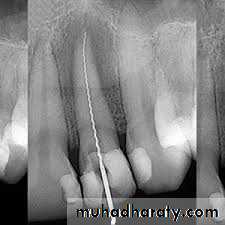

Microbial penetration in the canal treatment schedule can occur :

during treatment,between appointments,

or even after root canal obturation.The main causes of microbial introduction into the canal during treatment include:

• remnants of dental biofilm,• or caries on the tooth crown;

• leaking rubber dam;

• contamination of endodontic instruments (e.g., after touching with the fingers);

• and contamination of irrigant solutions or other solutions of intracanal use (e.g., saline solution, distilled water, citric acid).